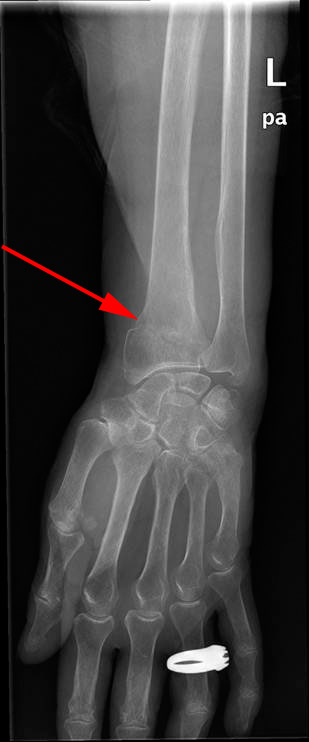

Metafysär fraktur som vanligen är dorsalbockad (distala fragmentet vinklas dorsalt) och ihoptryckt. Kallas Colles fraktur. - Det finns även komminuta varianter av dessa frakturer (flera frakturfragment). Icke-ledengagerande fraktur av radius, t ex den vanliga ihoptryckta dorsalt felvinklade metafysära radiusfrakturen (Colles fraktur), vilken ses ff a hos personer med osteoporos efter fall på utsräckt hand.